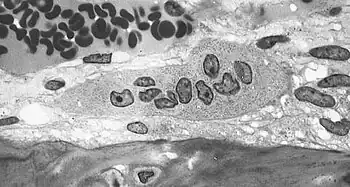

Collagen fibers of woven bone -

Osteoclast displaying many nuclei within its "foamy" cytoplasm. -